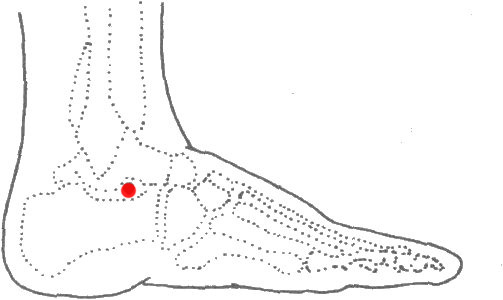

8 丘墟穴的定位

標準定位:丘墟穴在足外踝的前下方,當趾長伸肌腱的外側凹陷處。足少陽膽經的原穴[5]。

丘墟穴位於足外踝前下方,當趾長伸肌腱的外側凹陷處。伸足取之[5]。

丘墟穴位於足背外側,外踝前下緣,當趾長伸肌腱外側凹陷處[5]。

9 丘墟穴的取法

正坐垂足着地或側臥位,在外踝前下方,當趾長伸肌腱的外側凹陷處取穴。

丘墟穴位於足外踝前下方,當趾長伸肌腱的外側凹陷處。伸足取之[5]。